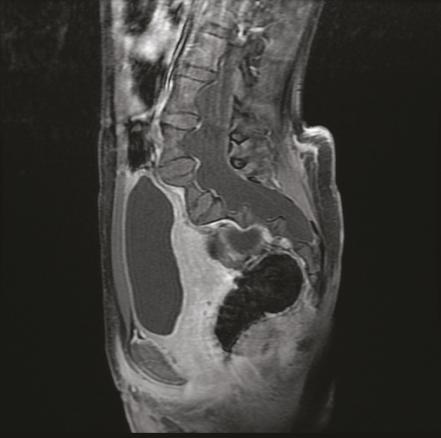

Cette jeune patiente de 12 ans atteinte d’une neurofibromatose de type 1 consultait pour des lombosciatalgies gauches. L’échographie pelvienne montrait une formation latéro-utérine droite cloisonnée. L’imagerie par résonance magnétique (IRM) pelvienne notait la présence d’une ectasie durale (fig. 1 ) responsable d’un festonnage (scalloping) [fig. 2 ] des parois des vertèbres lombosacrées, de même signal que le liquide céphalorachidien en hyposignal T1, hypersignal T2, sans rehaussement après injection de chélates de gadolinium, associée à des méningocèles élargissant les trous de conjugaison (fig. 1 ), fusant à travers les foramens intervertébraux en regard de L5 avec une extension paravertébrale antérieure. En l’absence de signe déficitaire, un traitement antalgique avec surveillance était prescrit, suivi d’une amélioration clinique.

Dans la neurofibromatose de type 1, l’ectasie durale est attribuée à une dysplasie mésodermique primitive des méninges. L’expansion des méninges sous l’effet des pulsations du liquide cérébrospinal provoque un scalloping sur la face postérieure des corps vertébraux et des hernies du sac méningé au travers des foramens intervertébraux.1 Le scalloping est observé dans la neurofibromatose dans 10 % des cas1 mais également dans le syndrome de Marfan, le syndrome d’Ehlers-Danlos et dans la spondylarthrite ankylosante. L’élargissement du canal rachidien et des foramens, la cyphose, la scoliose peuvent s’y associer.1 Les complications sont des déformations et dislocations vertébrales. Un déficit neurologique est rare.2